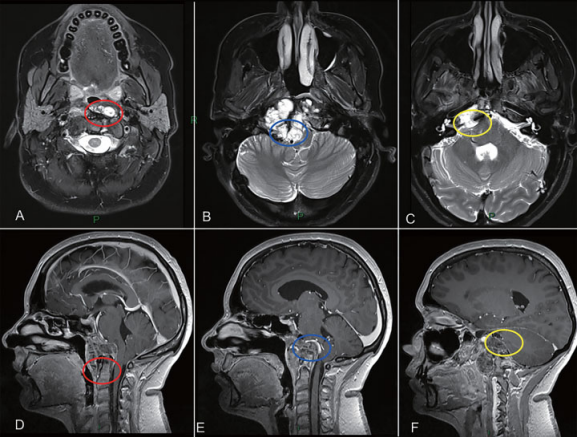

颅颈交界区肿瘤手术治疗策略分析,肿瘤的旁正中部分可以通过经鼻内镜手术切除。枢椎齿状突周边肿瘤(A和D处红色圆圈)、侵犯硬膜内部分的肿瘤与后循环接触(B和E处蓝色圆圈)和先前乙状窦后入路手术的粘连(C和F处黄色圆圈),这些部位的肿瘤更适合二期远外侧开颅手术。